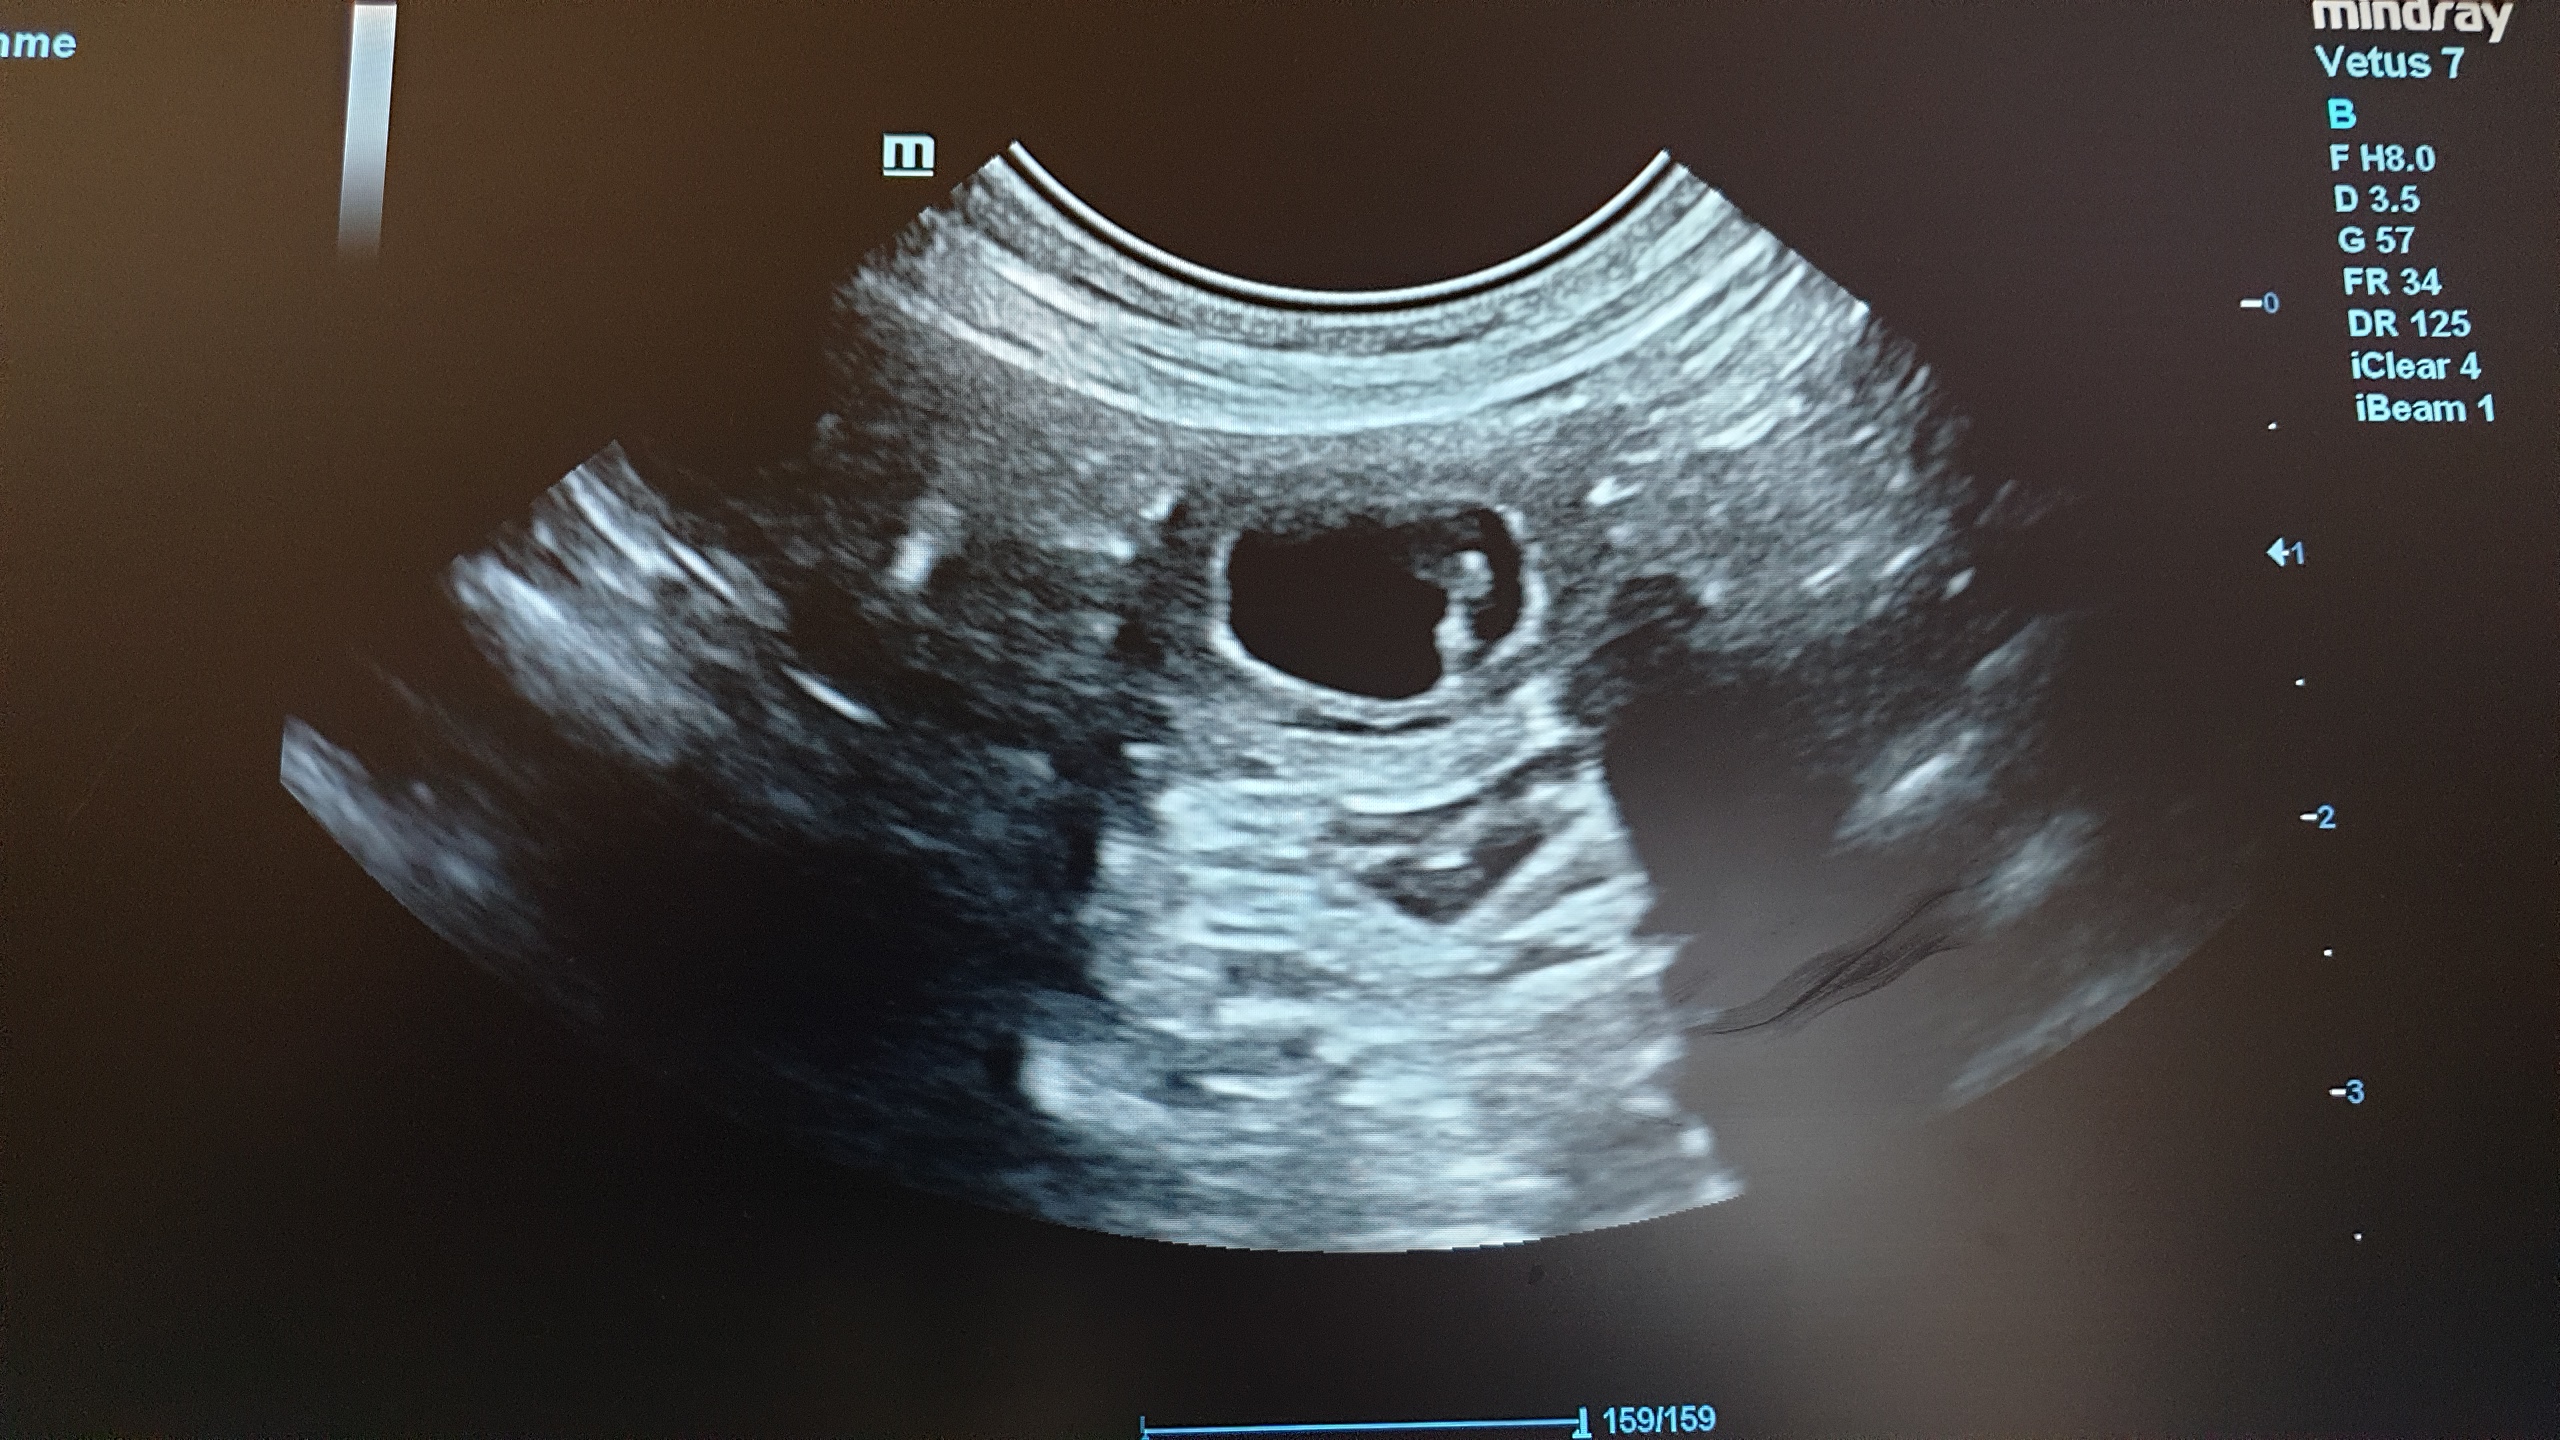

Aslana spielt wieder gerne, frisst aber immer noch sehr mäkelig. Ihr Gewicht ist ebenfalls unverändert. Und nun ist auch der Ultraschall dran:

Aslana ist wieder trächtig! Gezählt habe ich 6-7 Welpen, das lässt sich aber im Ultraschall nicht genau sagen, weil man nicht alle Welpen auf ein Bild bekommt. Wir freuen uns auf die kommenden Wochen :o).